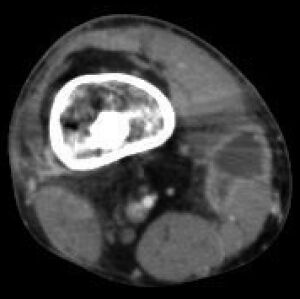

Radiographs and CT are the initial method of diagnosis, but are not sensitive and only moderately specific for the diagnosis. They can show the cortical destruction of advanced osteomyelitis, but can miss nascent or indolent diagnoses.[23]

Confirmation is most often by MRI.[24] The presence of edema, diagnosed as increased signal on T2 sequences, is sensitive, but not specific, as edema can occur in reaction to adjacent cellulitis. Confirmation of bony marrow and cortical destruction by viewing the T1 sequences significantly increases specificity. The administration of intravenous gadolinium-based contrast enhances specificity further. In certain situations, such as severe Charcot arthropathy, diagnosis with MRI is still difficult.[23] Similarly, it is limited in distinguishing avascular necrosis from osteomyelitis in sickle cell anemia.[25]

Nuclear medicine scans can be a helpful adjunct to MRI in patients who have metallic hardware that limits or prevents effective magnetic resonance. Generally a triple phase technetium 99 based scan will show increased uptake on all three phases. Gallium scans are 100% sensitive for osteomyelitis but not specific, and may be helpful in patients with metallic prostheses. Combined WBC imaging with marrow studies has 90% accuracy in diagnosing osteomyelitis.[26]

Diagnosis of osteomyelitis is often based on radiologic results showing a lytic center with a ring of sclerosis.[13] Culture of material taken from a bone biopsy is needed to identify the specific pathogen;[27] alternative sampling methods such as needle puncture or surface swabs are easier to perform, but cannot be trusted to produce reliable results.[28][29]